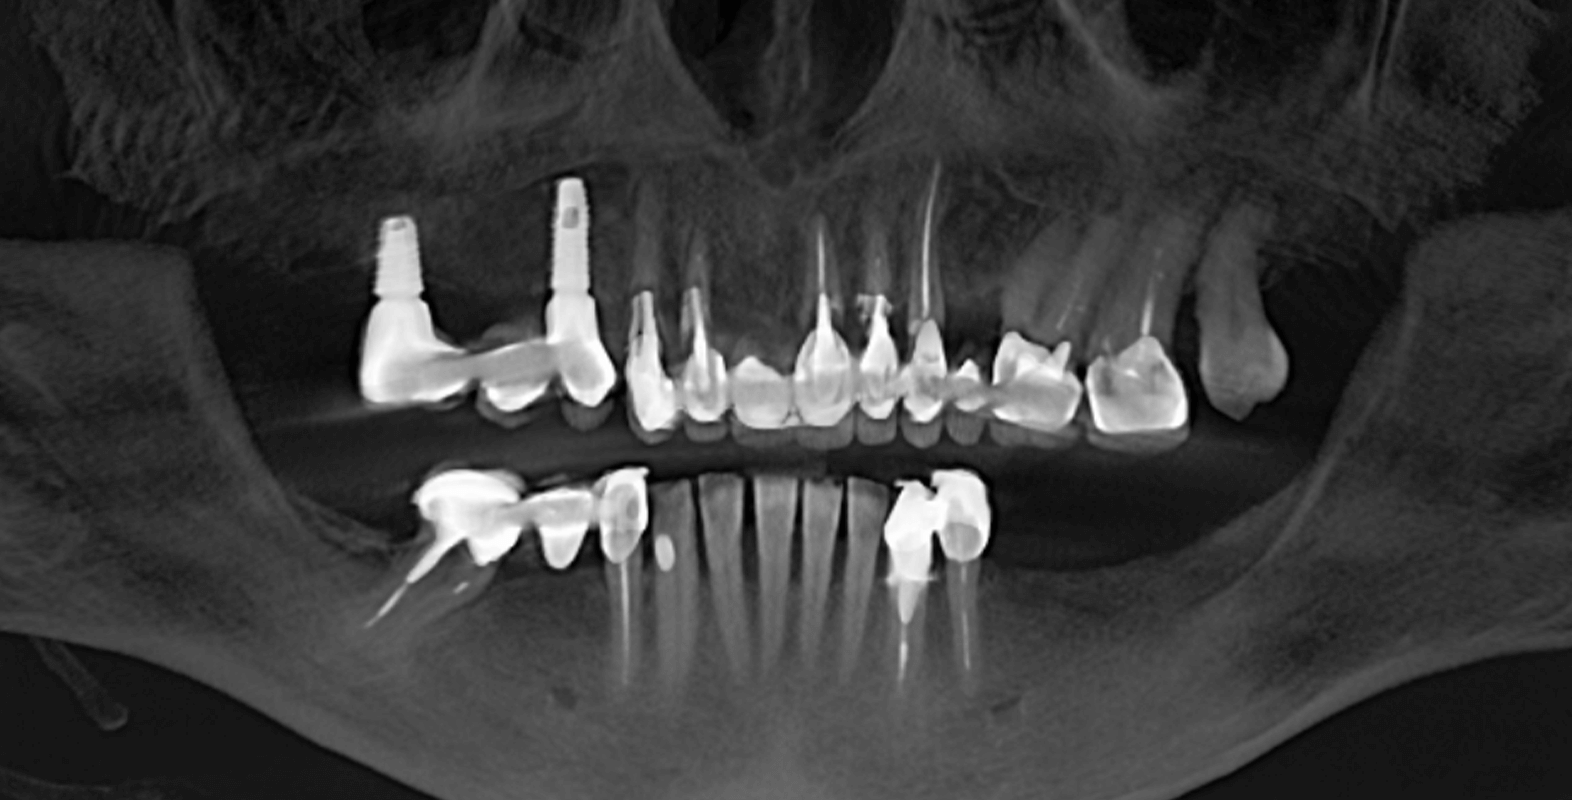

После анализа данных полученных путем компьютерной томографии и при очном осмотре было обнаружено:

- Установленный мостовидный протез на зубах 4.4 и 4.6 (зуб 4.5 отсутствует).

- Зубные коронки на зубах 3.3 и 3.4

- Зубы 3.6 и 3.7 отсутствуют.

- Имплантаты в области недостающих зубов 1.4, 1.6 и металлокерамический мостовидный протез на них с винтовой фиксацией.

- На зубах 1.3, 1.2, 2.1, 2.2, 2.3, 2.6 и 2.7 (2.4 и 2.5 отсутствуют) установлен металлокерамический мостовидный протез на родных зубах, который был подвижен и снимался вместе с вкладками.

- Зубы 1.2, 1.3 и 2.1 расколоты.

- Зуб 1.5 отсутствует.

- Кариозное поражение зуба 2.8

- Зубы 1.6 и 1.7 депульпированы.

- Катаральный гингивит на слизистой верхней челюсти (как следствие регулярного раздражения от подвижного металлокерамического протеза).